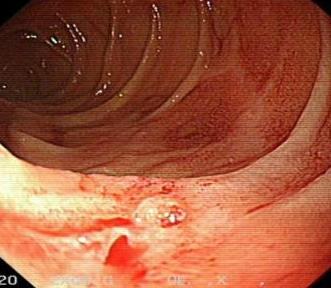

• 结直肠腺瘤住院患者胃镜检查的临床资料分析(附1 052例报告)

2026, 32(1):26-34. DOI: 10.12235/E20250190

摘要:目的 分析1 052例结直肠腺瘤住院患者行胃镜检查的资料,以期为结直肠腺瘤患者上消化道黏膜病变的早期发现和治疗提供参考依据。方法 回顾性分析2023年1月1日-2023年12月31日在九江学院附属医院消化内科住院的1 052例结直肠腺瘤患者的临床资料,分析患者临床表现、结肠镜结果、胃镜结果和疾病类型分布。结果 1 052例患者均伴随消化不良、胃肠道功能异常、胃食管反流和消化道出血症状,均检查出上消化道黏膜疾病,检出率为100.00%,192例(18.25%)患者只有1个胃镜诊断结果,860例(81.75%)患者有2个或2个以上诊断结果。共检出1 881处病变,以胃黏膜病变为主,其次为食管黏膜病变和十二指肠黏膜病变。前三检出疾病分别为:慢性非萎缩性胃炎932处,胃黏膜糜烂和/或胃肠上皮化生344处,以及胃息肉219处。不同性别疾病类型分布特点:大部分男性食管黏膜病变、胃黏膜病变和十二指肠黏膜病变占比高于女性,男性食管炎占比高于女性;不同年龄段疾病类型分布特点:年龄 > 45岁的患者胃息肉增多;Kaplan-Meier生存曲线显示,与未行胃镜检查的结直肠腺瘤患者相比,行胃镜检查的结直肠腺瘤患者无复发时间更长(HR^ = 13.103,95%CI:6.589~26.057,P < 0.01)。结论 结直肠腺瘤患者建议行胃镜检查,以明确是否存在上消化道黏膜疾病。 > 45岁和男性为高风险人群,建议定期检查,通过早期发现和治疗,预防此类人群上消化道黏膜病变的发生。